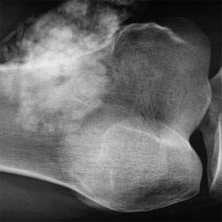

МРТ костей таза показывает множественные очаги, что говорит о метастатическом поражении

Магнитно-резонансное сканирование с контрастированием улучшает возможности визуализации. Исследование с усилением проводят для диагностики опухолевого процесса, включая обнаружение метастазов в костях таза, раннего выявления рецидива новообразования после лечения, уточнения степени выраженности воспалительного процесса, деструкции и пр. Контраст на основе гадолиния обладает высоким профилем безопасности и не требует предварительной оценки функции почек. Побочные эффекты на введение парамагнетика регистрируют крайне редко. В 99,9 % случаев исследование проходит без осложнений. Противопоказания к контрастированию: